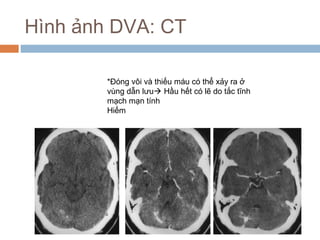

Hình ảnh DVA: CT

*Đóng vôi và thiếu máu có thể xảy ra ở

vùng dẫn lưu Hầu hết có lẽ do tắc tĩnh

mạch mạn tính

Hiếm